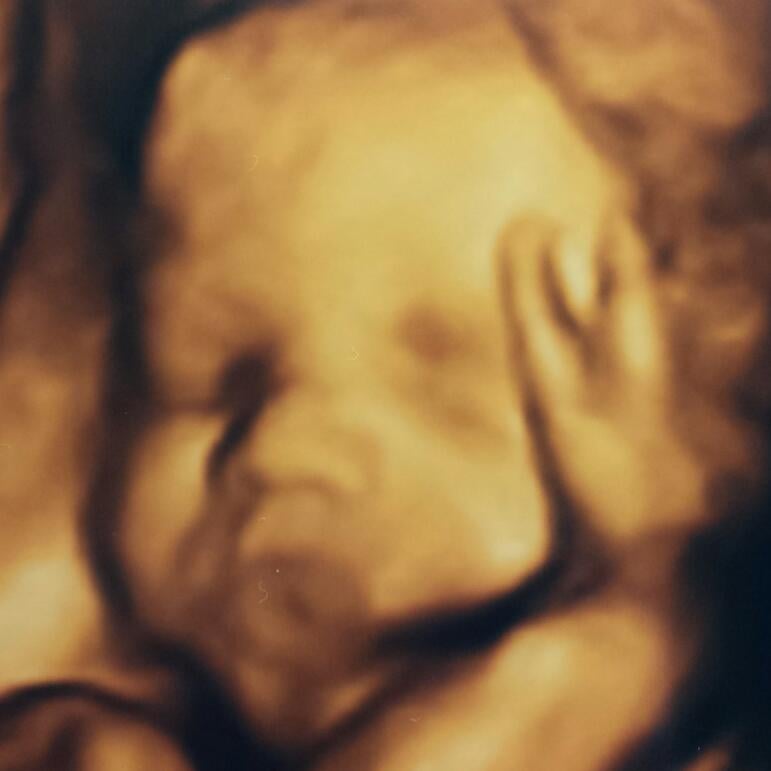

I feel the same way! I'm a photo junkie for sure and I too have been disappointed with ultrasounds pics of LO. I got good shots from my 20 week anatomy scan (below), but that's it from the whole pregnancy so far. I've had to ask for 2 out of the 3 other ultrasounds I've had and one of she she was just an embryo lol. The two I asked for are hard to see her. My MIL bought me a session so her, my mom, myself and my husband could go and see her sweet little face together for the holidays.

• I LOVE the 3d/4d :( the benefit is that most of the time of you do not get a good session most places Ive gone give second sessions free of charge. Ive done it with both my boys. :) my first born on left and 2Nd on right :)

• 32 weeks. She has chubby cheeks